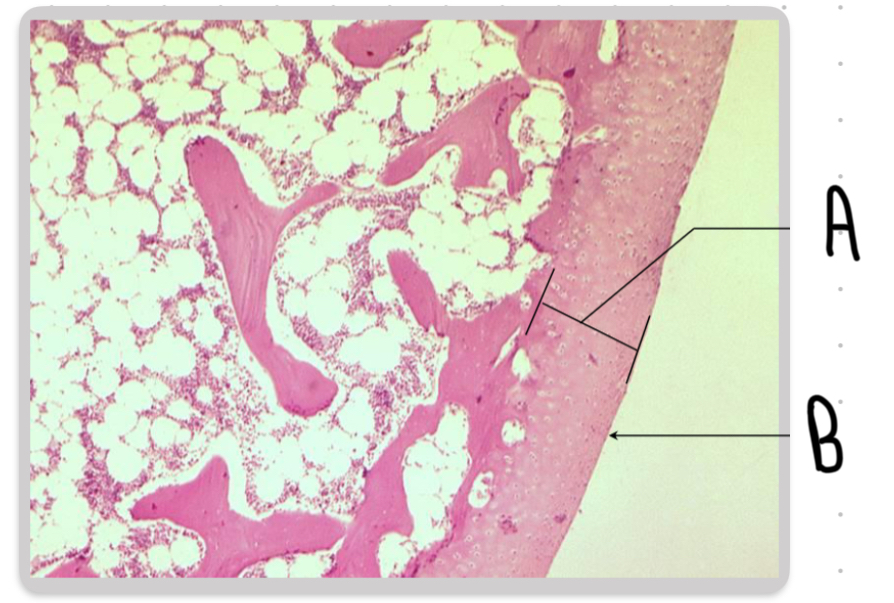

What is the structure labeled A in this image?

Hyaline cartilage

Name the structure labeled B in this image:

The articular surface.